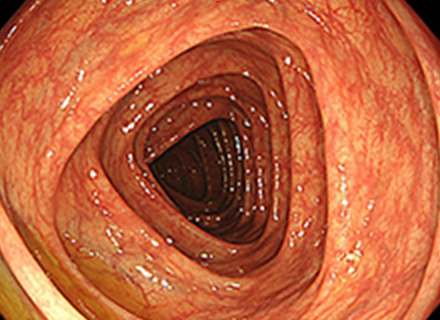

下部消化管(大腸カメラ)内視鏡検査では、肛門より太さ約13~14mmの内視鏡スコープを挿入し、空気(炭酸ガス)の注入を行いながら大腸のヒダをたぐり寄せて盲腸まで挿入します。 盲腸へ到達後、ポリープやがん、炎症などの病気がないか観察しながら内視鏡スコープを抜いてきます。 途中で病変が見つかった場合は、必要に応じて病変の一部を採取(生検)して調べたり、ポリープや早期がんなどの病変を内視鏡的に切除することもできます。検査時間は通常10~15分程度ですが、ポリープを切除すると通常より時間は長くかかります。